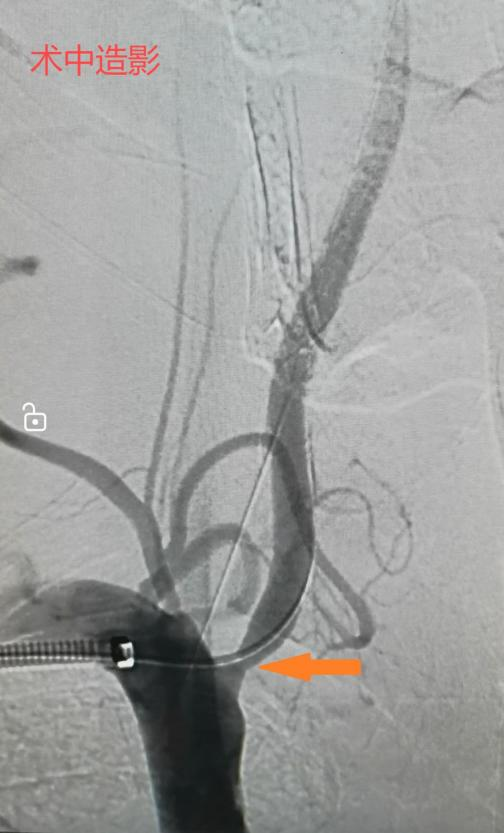

手术过程中,血管外科执行主任李鑫使用如头发丝粗细的导丝迅速通过病变段狭窄建立治疗轨道,沿着这根轨道将一枚精细的血管支架精准无误地放置在病变部位的血管,使得之前闭塞了80%的管腔恢复到了正常的血液供应水平。整个手术过程不到半小时,而唯一的“创伤”就是右手肘部的一个小小针眼。术后,王大叔的头晕、头疼及黑矇等症状均得到了明显缓解,生活质量得到了显著提高。

此外,对于接受腔内支架置入术的患者来说,术后的护理和随访同样重要。患者需要按时服用一段时间的抗凝、抗血小板等药物,以预防血栓形成和血管再狭窄;同时,定期进行复查,以便医生及时了解患者的恢复情况并调整治疗方案。血管支架的植入是很多心血管疾病有效的治疗方案,能够微创、高效地“保命”和降低致残概率,我们大可不必“谈支架色变”。